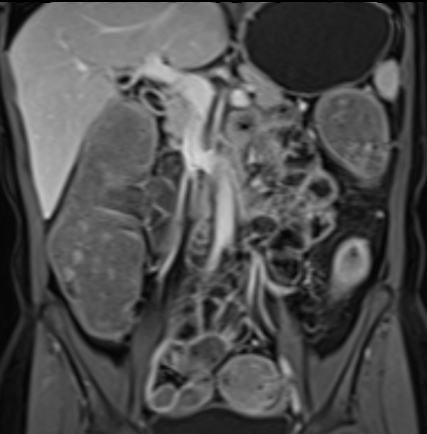

Bệnh nhân nữ 48 tuổi, đang điều trị bằng thuốc kháng TNF, được chỉ định nội soi đại tràng.

Phát hiện hẹp lòng ruột ở đại tràng sigma, không thể vượt qua được khi nội soi.

MR-enterography được thực hiện để đánh giá mức độ lan rộng của chỗ hẹp.

Ruột non bình thường, nhưng ghi nhận các đoạn hẹp ở đại tràng xuống và đại tràng ngang.

Cả hai đoạn hẹp đều có thành ruột dày đến 8 mm và ngấm thuốc rõ rệt theo kiểu niêm mạc ở đại tràng xuống và kiểu phân lớp ở đại tràng ngang.

Giãn ruột trước chỗ hẹp được ghi nhận ở cả hai đoạn.

Do các chỗ hẹp này không hiện diện khi nội soi đại tràng trước khi điều trị kháng TNF, nhiều khả năng chúng đã hình thành trong quá trình điều trị.

Do đó, quyết định phẫu thuật cắt đại tràng gần toàn bộ với miệng nối hồi-sigma đã được đưa ra.